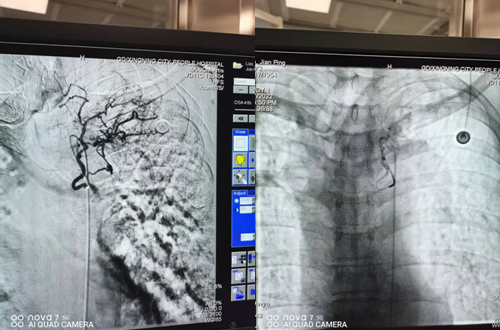

左侧支气管动脉栓塞前后

右侧支气管动脉栓塞前后 手术历经约2小时顺利完成,手术结束后,廖先生的咯血立刻被止住,当天晚上终于睡上了一个安稳觉。术后廖先生在科室医护人员的精心治疗和护理下病情康复良好,准备出院时家属送来锦旗,深表谢意!